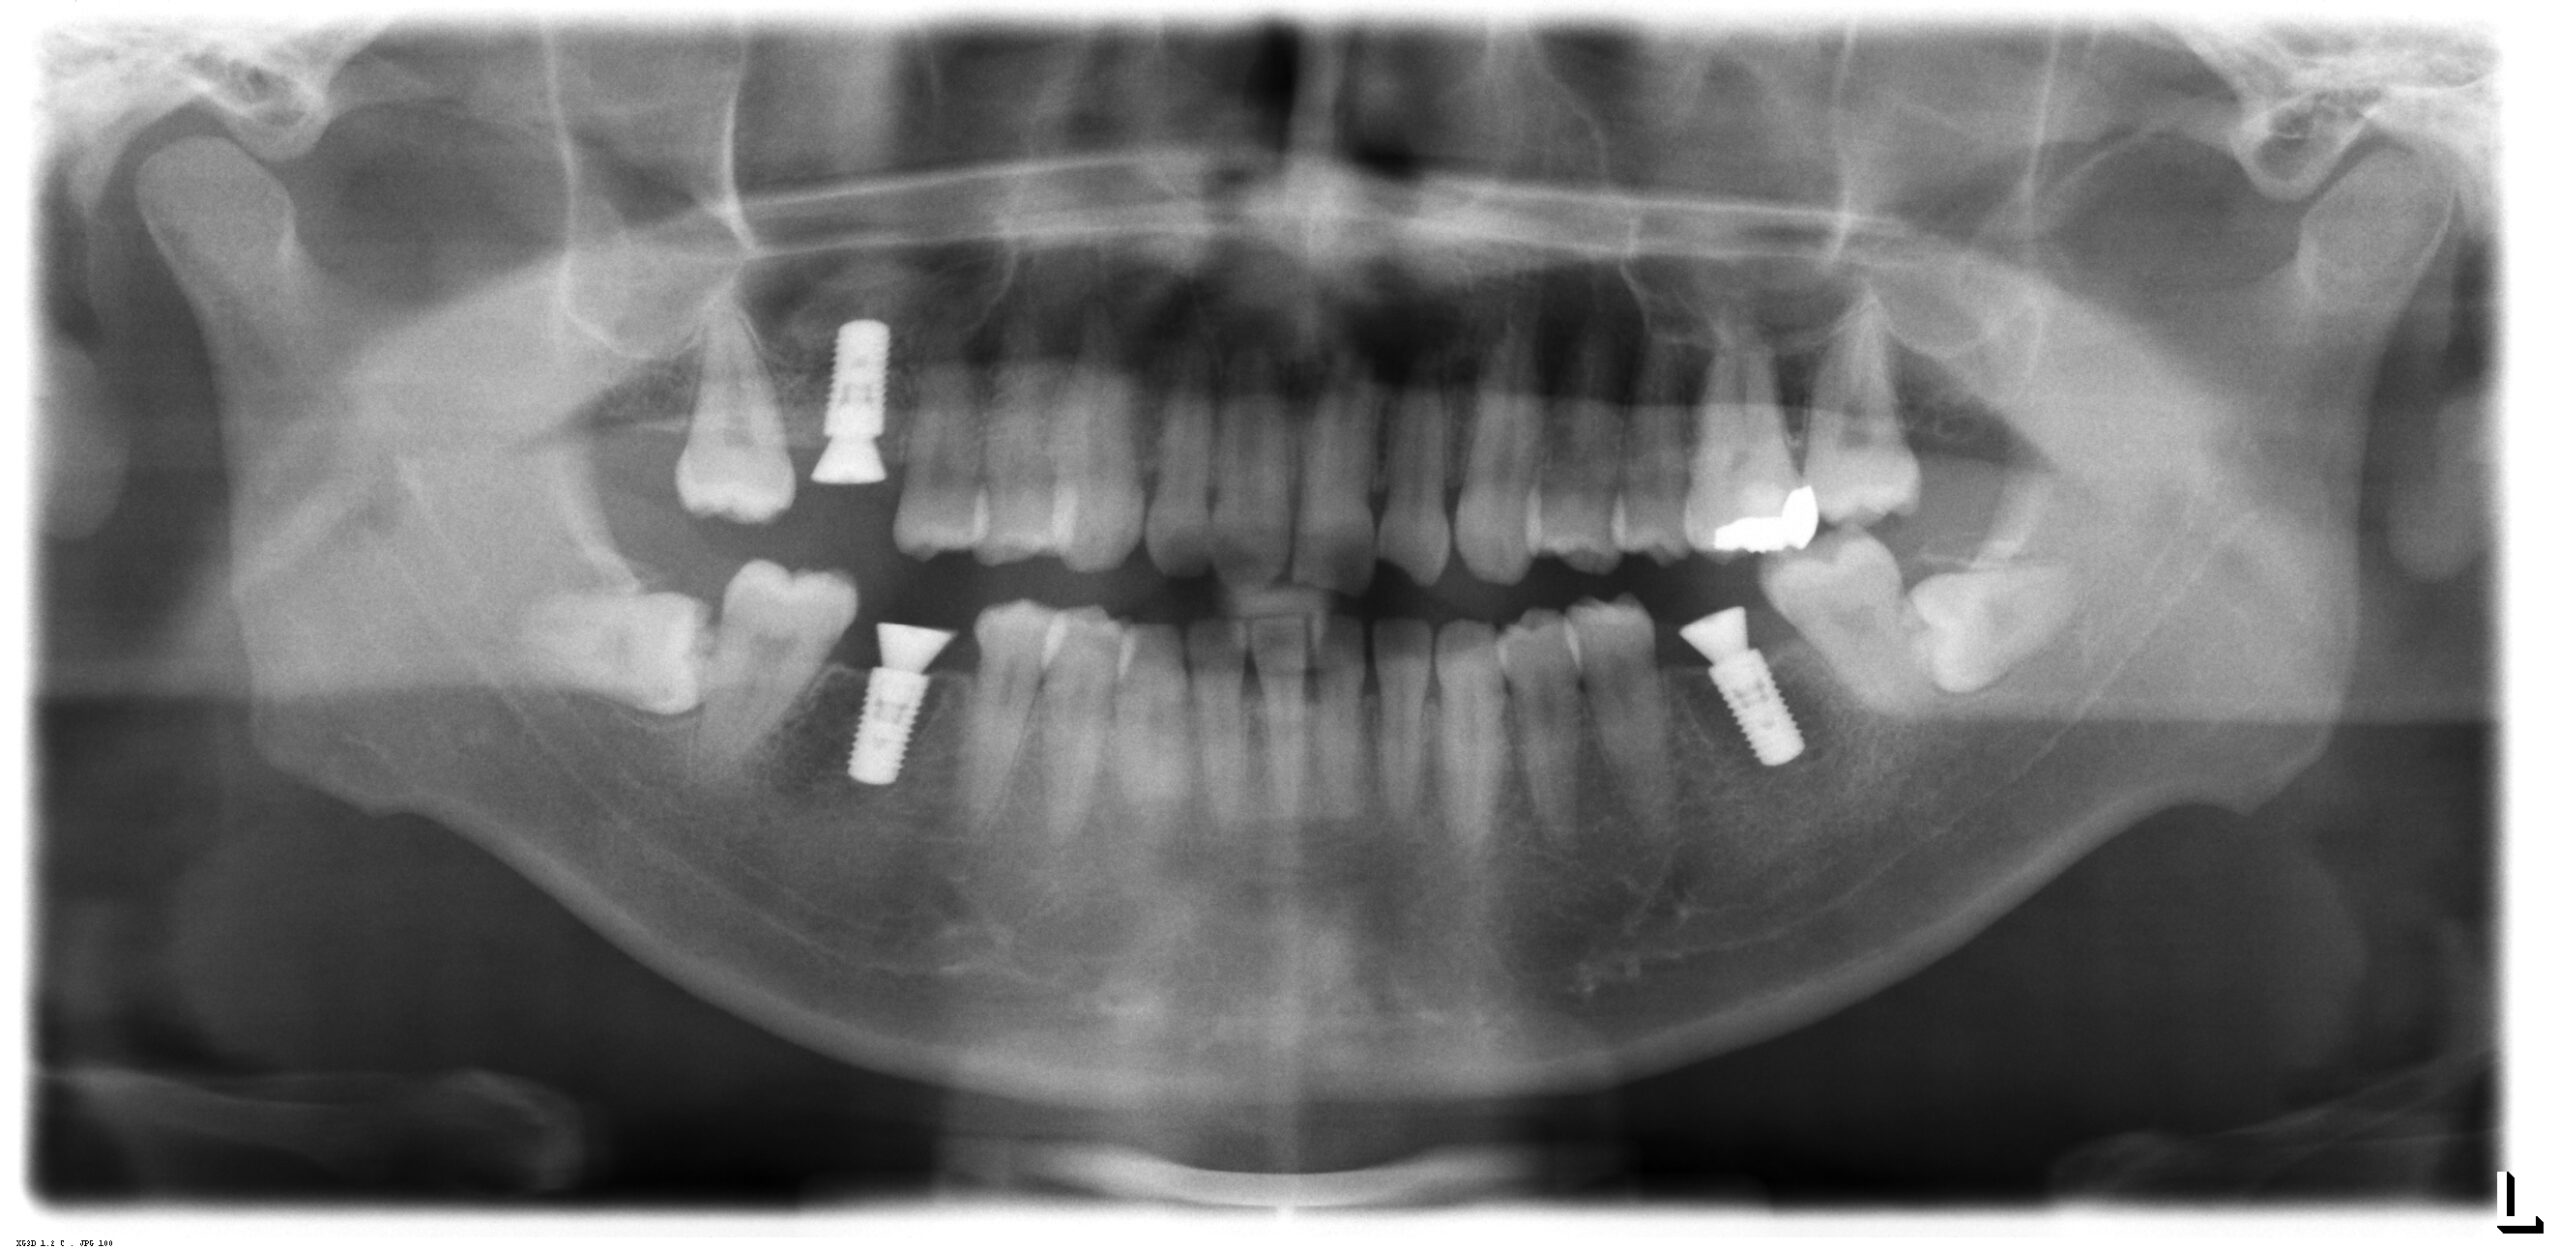

上部構造が装着された後のレントゲン写真です。